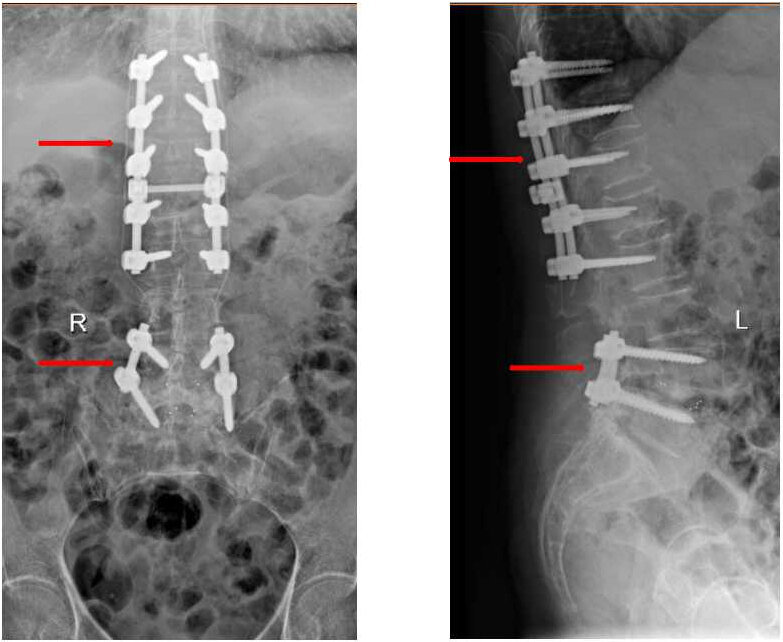

陈奶奶术后复查X线,上箭头为本次手术固定装置,下箭头为既往手术固定装置

看这个MRI和CT的结果,T12和L1这两个地方的压缩性骨折肯定没跑了,但是这个骨折有一小部分压迫到了脊髓和神经,失去了打骨水泥这种微创手术的机会。不得不做了一个大的开放性的后路T12、L1椎体骨折切开复位内固定术。又给加了5对也就是10个钉子在里面。